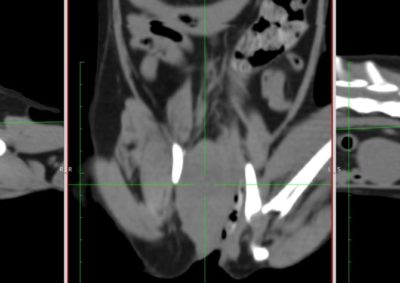

腫瘍外科 注意 ボタンをクリックした先に、治療中および手術中の画像が説明で使用されている場合がございます。 そのような画像に弱い方は閲覧なさらないようお願いいたします。 腫瘍外科 犬の甲状腺癌 軟部組織外科腫瘍外科 唾液腺癌 Salivary gland carcinoma 軟部組織外科腫瘍外科 胃部分切除術・ビルロートI 腫瘍外科 MLO 多小葉性骨腫瘍 腫瘍外科 軟部組織肉腫 G3 軟部組織外科腫瘍外科 直腸プルスルー 内科腫瘍外科 尾状葉乳頭突起に限局した高分化型肝細胞癌 内科腫瘍外科 猫の消化管型リンパ腫(腸穿孔を伴う) 腫瘍外科救急・集中治療 腹腔内出血 内科腫瘍外科救急・集中治療 細菌性腹膜炎 腫瘍外科 肝臓原発血管肉腫 腫瘍外科 犬の原発生肺癌(左) <1234567> 症例カテゴリー 放射線治療整形外科軟部組織外科脳神経外科内科腫瘍外科救急・集中治療リハビリテーション科腫瘍内科内視鏡科脳神経科呼吸器外科中医・漢方猫の腎移植循環器科